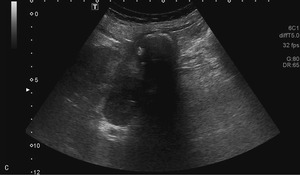

63-letnią kobietę przyjęto na oddział chirurgiczny z przewlekłymi bólami brzucha nasilającymi się w ostatnich 3 tygodniach. Od tygodnia obserwowano zażółcenie powłok, wymioty, odbarwienie stolca i brak łaknienia, co sugerowało żółtaczkę mechaniczną. W ciągu ostatnich 2 miesięcy masa ciała pacjentki zmniejszyła się o 8 kg. Na podstawie wcześniejszych badań USG, wykonanych 10 i 12 lat temu, rozpoznano u niej kamicę pęcherzyka żółciowego. Żółtaczkę potwierdzono w badaniach laboratoryjnych. Wykazano w nich także leukocytozę oraz podwyższone stężenie dimera D i CRP. W wykonanym przy przyjęciu badaniu USG zaobserwowano liczne złogi w pęcherzyku żółciowym i pogrubienie jego ściany z nieregularnym hiperechogenicznym naciekiem w sąsiadującym miąższu wątroby. Stwierdzono także poszerzenie dróg żółciowych wewnątrzwątrobowych w obrębie prawego płata oraz obecność niewielkiej ilości wolnego płynu w jamie otrzewnej (ryc. 1A, B). W dnie pęcherzyka uwidoczniono silne echo zlokalizowane w zarysie ściany narządu (ryc. 1C).

Wszystkie przedstawione warianty rozpoznania są prawdopodobne. Obraz USG z ryciny 1C sugeruje obecność złogu poza obrysem zmienionego zapalnie pęcherzyka żółciowego (rozpoznanie kamicy jest oczywiste na podstawie wcześniejszych obrazów). Bezdyskusyjne jest także rozpoznanie rozległego nacieku, prawdopodobnie zapalnego, w ścianie i w sąsiedztwie pęcherzyka. Fakt ten mocno uprawdopodabnia wytworzenie odleżyny w dnie pęcherzyka, perforacja jego ściany i migracja złogu do jamy otrzewnej.